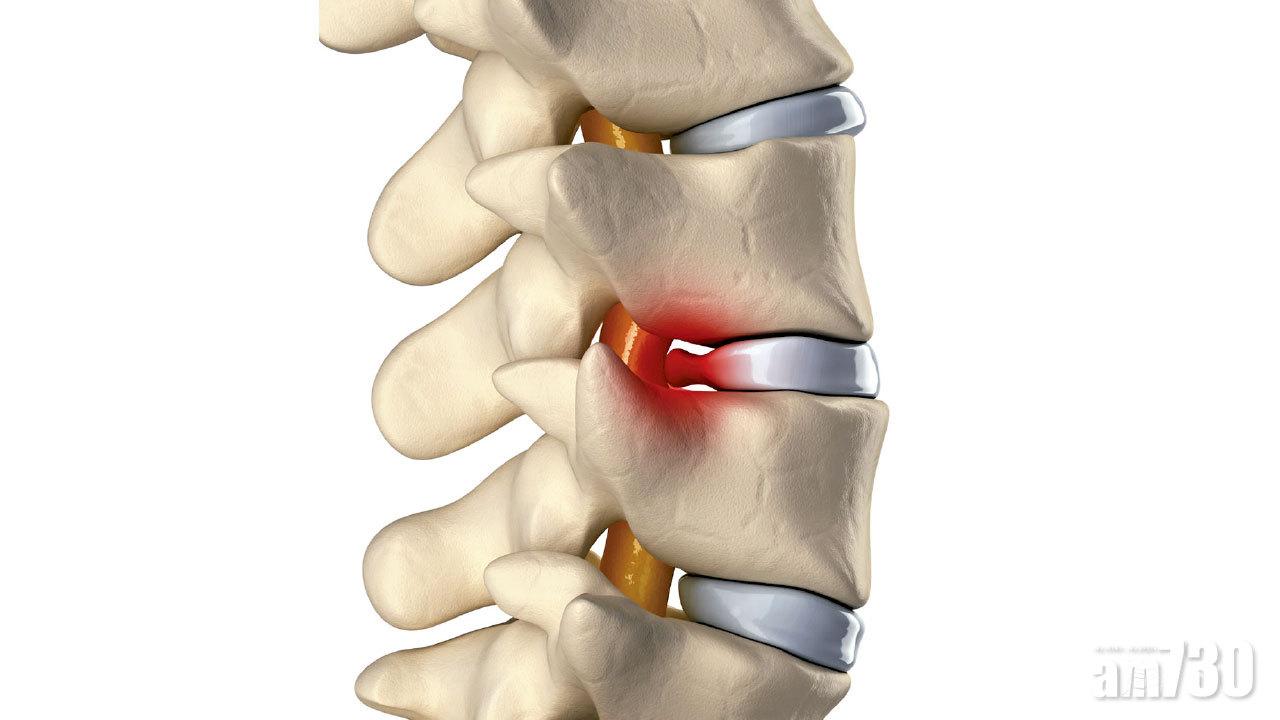

人體脊椎從側面看,呈雙S形,負重承托身體。日常生活裡,我們每個動作都由脊骨支持,每節脊骨之間是椎間盤,好像「水泡」般,由纖維膜包著液體,作用如咕𠱸「吸震」,除了緩衝體重的負荷外,也可以容許身體捲曲。

但隨着年紀大出現退化、長期姿勢不當、過劇運動或創傷等,會令椎間盤受壓破裂,或者從脊骨之間被擠壓出來,形成椎間盤突出。

且視乎突出的位置及臨床情況,可能形成骨刺、影響脊椎神經或脊髓等。患者可能感到腰骨痛、頸梗,嚴重者會麻痺,下半身無力,無法步行,甚至失禁。